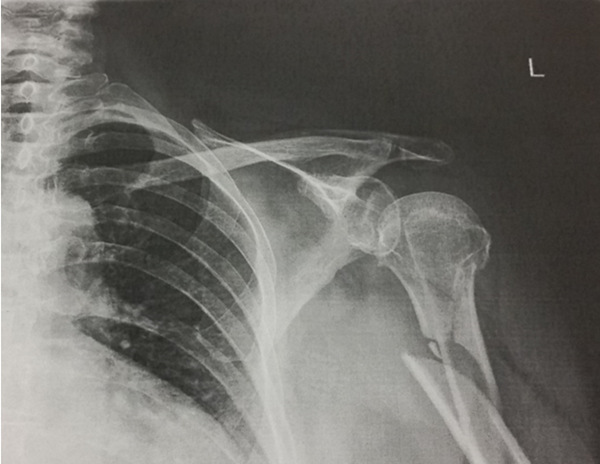

A broken bone is one of the most painful and disruptive injuries a person can experience. Bones such as the humerus, pictured above, can easily break and fracture during a serious accident. This particular X-ray was taken following an event where someone tripped and fell in one of our cases. However, similar injuries can and often do occur, including broken bones, during a car accident.

- Mid-Shaft Fractures: Along the middle of the bone, common in direct side-impact or rollover crashes. (This is the type of fracture sustained in the above X-ray image.)